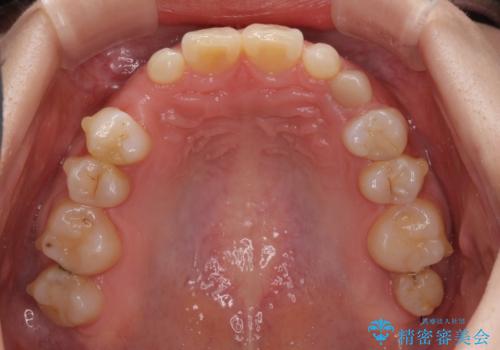

欠損と残存乳歯 矯正治療とインプラント治療

- 残存した乳歯や歯の欠損、歯並びを気にして来院された患者様です。

乳歯を残した状態は予後がよくないこと、矯正治療と補綴治療を総合的に進めていきたいとのことで、インビザラインによる矯正治療とインプラント補綴治療を並行して進めていくこととしました。

当院は矯正治療もインプラント補綴治療も、同一の歯科医師が担当するため、矯正治療を行いながら、最適なタイミングでインプラント補綴治療を行うことが可能です。